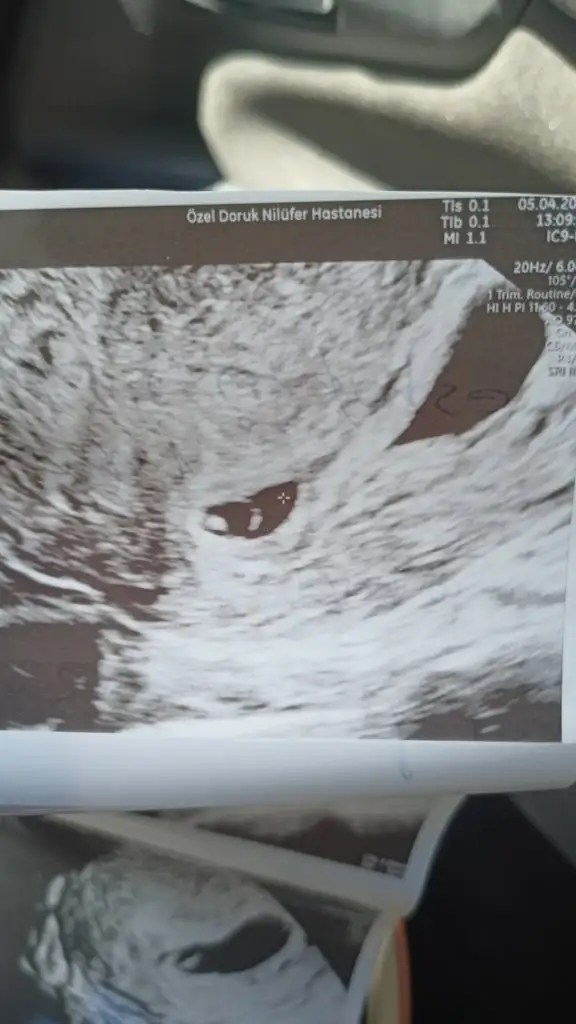

Özel Dr mu söyledi bunu devlet mi canımBilmiyorum kesede biraz bozulma var dedi bekliycezdedi igne yapdi bi tane proluton bi de progestan fitil yazdi sabah aksam bekliycez dedi dusede bilir bebek buyudukce duzelede bilir dedi yolk sac ve embiryo gorundu ama kesede biraz bozulma var dedi bilmiyorum hayirlisi Allahdan dua etmekden baska yapabilcem bise yok umarim duzelir

Hayir özele gittim cnm bak bu benim kese senin daha duz duruyo sanki baksanaÖzel Dr mu söyledi bunu devlet mi canım

Bak canım bana gittiğim özel prof dedi bu ultrason cihazını hareket ettirdikce onun görüntüsü değişir benim sonraki ultrason resmim yamuk yumuk birşey sen bol bol su iç dinlen bak bebeğin görünmüş bebeğe genetik pgt yapıldı mıHayir özele gittim cnm bak bu benim kese senin daha duz duruyo sanki baksana

Bak nasıl yamuk duruyor ama hareket ettirdiği için ultrasonda ben görmüştüm mesela yuvarlakti burda bir tuhaf bebeklerimUmarim bise olmaz kanam bida olmadi ama kesenin bozulmasina sasirdim proluton igne yapdi progestan fitil yazdi sabah aksam bekliycez dedi umarim bise olmaz duzelir

Rabbim korusun inslh hepimizin evladini inslh benimde duzelir bise olmaz tskr ederim sagolBak nasıl yamuk duruyor ama hareket ettirdiği için ultrasonda ben görmüştüm mesela yuvarlakti burda bir tuhaf bebeklerim